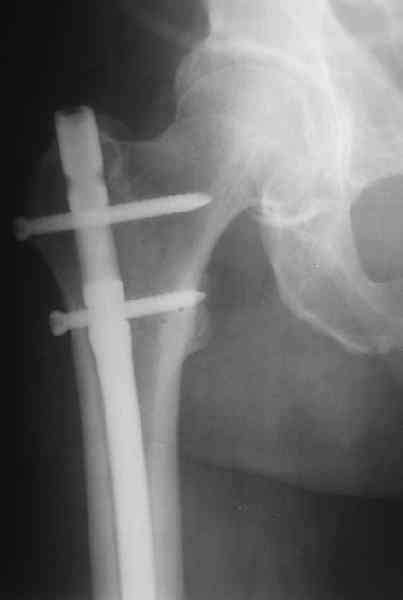

> Хотелось бы узнать какую тактику  лечения Вы предпочли? Речь идет о

> пациенте 60-ти лет с переломом  дистального отдела бедренной кости,

> фиксированного пластиной?

Удалили ластину без проблем. Выявилась значительная подвижность. В

этих условиях сразу пропала мотивация к постепенной коррекции аппаратом.

Попробовал восстановить длину, введя между отломками spreader. Отчасти

удалось. Тогда защили рану, наложили спицевой дистрактор (2 спицы в

дистальный отдел и 1 вверху). после этого был убран и спонгиозный

винт. И сделали антгерадное штифтование, как говорится, "по принятой в

клинике методике".

Дполнительные доступы для введения гвоздя и проксимальных винтов

понадобились, но они маленькие, по 1 см. Нижние винты ввели прямо

между швами. Суставы дополнительно не травмировали, и даже ввели

гвоздь не через f. piriformis, а через большой вертел.

Длину восстановили, возможно, даже с изьбытком, ну да динамизируем

пораньше. Введенные в овальное отверстие  дистальые винты имеют

угловую стабильность.  Снимки приложены. Заранее спасибо за критику и

комментарии.